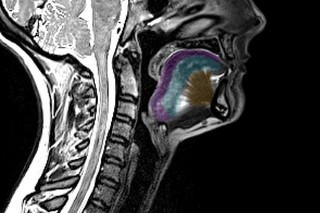

VIDEO Chirurgia intră în era 3D: cum sunt folosite hologramele pentru a planifica intervenţii complexe 26 nov 2025